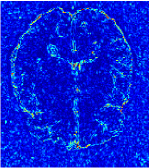

All the experiments are implemented on a Windows workstation with Intel Core i9 CPU at 3.3GHz and an Nvidia GTX-1080Ti GPU with 11GB of graphics card memory via TensorFlow Abadi et al. (2016). The parameters in the proposed network are initialized by using Xavier initialization Glorot and Bengio (2010). We trained the meta-learning network with four tasks synergistically associated with four different CS ratios: 10%, 20%, 30%, and 40%, and test the well-trained model on the testing dataset with the same masks of these four ratios. We have 300 training data for each CS ratio, which amount to total of 1200 images in the training dataset. The results for and MR reconstructions are shown in Tables 5.4 and 5.4 respectively. The associated reconstructed images are displayed in Figures 1 and 3. We also test the well-trained meta-learning model on unseen tasks with radio masks for skewed ratios: 15%, 25%, 35%, and random Cartesian masks with ratios 10%, 20%, 30% and 40%. The task-specific parameter for the unseen tasks are retrained for different masks with different sampling ratios individually with fixed task-invariant parameters . In this experiments, we only need to learn for three skewed CS ratios with radio mask and four regular CS ratios with Cartesian masks. The experimental training proceed on less data and iterations, where we performed on 100 MR images with 50 epochs. For example, for reconstructing MR images with CS ratio 15% radio mask, we fix the parameter and retrain the task-specific parameter on 100 raw data with 50 epochs, then test with renewed on our testing data set with raw measurement that sampled from radio mask with CS ratio 15%. The results associated with radio masks are shown in Table 5.4 and 5.4, Figure 2 and 4 for and images respectively. The results associated with Cartesian masks are list in Table 5.4 and reconstructed images are displayed in Figure 5.

In this section, we test the generalizability of the proposed model that tests on unseen tasks. We fix the well-trained task-invariant parameter and only train for sampling ratios 15%, 25% and 35% with radio masks and sampling ratios 10%, 20%, 30% and 40% with Cartesian masks. In this experiment, we only used 100 training data for each CS ratio and apply a total of 50 epochs. The averaged evaluation values and standard deviations are listed in Table 5.4 and 5.4 for reconstructed T1 and T2 brain images respectively that proceed with radio masks, and Table 5.4 shows the qualitative performance for reconstructed T2 brain image that applied random Cartesian sampling masks. In T1 image reconstruction results, meta-learning improved 1.6921 dB in PSNR for 15% CS ratio, 1.6608 dB for 25% CS ratio, and 0.5764 dB for 35% comparing to the conventional method, which in the tendency that the level of reconstruction quality for lower CS ratios improved more than higher CS ratios. A similar trend happens in T2 reconstruction results with different sampling masks. The qualitative comparisons are illustrated in Figure 2, 4 and 5 for T1 and T2 images tested in skewed CS ratios in radio masks, and T2 images tested in Cartesian masks with regular CS ratios respectively. In the experiments that conducted with radio masks, meta-learning is superior to conventional learning especially at CS ratio 15%, one can observe that the detailed region in red boxes keeps edges and is more close to the true image, while conventional method reconstructions are hazier and lost details in some complicated tissue. The point-wise error map also indicates that Meta-learning has the ability to suppress noises.